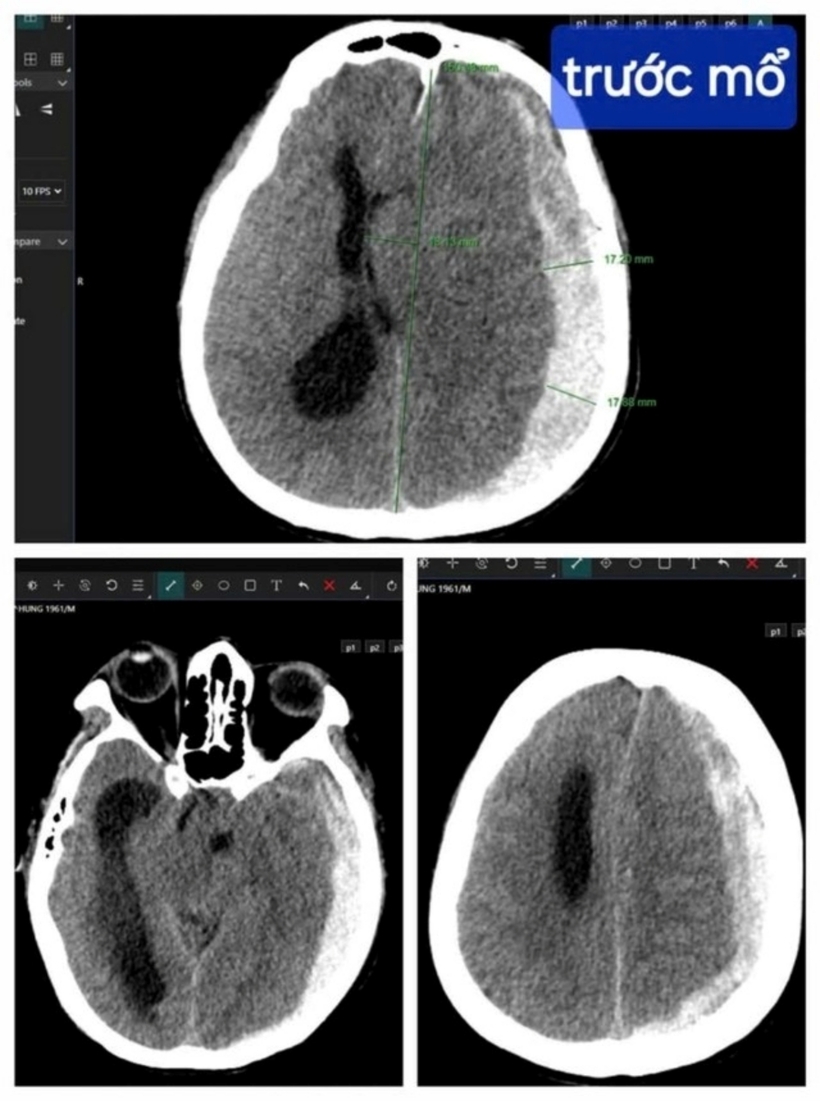

Cứu người đàn ông 63 tuổi bị tụ máu não nguy kịch

Theo Người Đưa Tin Pháp Luật, ngày 26/9, thông tin từ Bệnh viện Hữu nghị Việt Nam – Cuba Đồng Hới (tỉnh Quảng Bình), các y, bác sĩ tại bệnh viên vừa cứu sống thành công một người đàn ông nhập viện trong trạng thái nguy kịch.

Cụ thể, trung tuần tháng 9, nam bệnh nhân P.V.H. (63 tuổi) được người nhà đưa đến nhập viện tại khoa Ngoại thần kinh Bệnh viện Hữu nghị Việt Nam – Cuba Đồng Hới, với chấn thương ở vùng đầu.

Khai thác tiền sử, người nhà bệnh nhân cho biết, trước đó ông H. bị ngã rồi về nhà nằm ngủ. Sau đó, người nhà gọi mãi không thấy ông H. dậy, kiểm tra thì phát hiện ông H. hôn mê nên đưa ngay đến bệnh viện.

Ths.BS Nguyễn Mạnh Linh ở khoa Ngoại Thần kinh Bệnh viện Hữu nghị Việt Nam – Cuba Đồng Hới chia sẻ, thời điểm tiếp nhận, bệnh nhân hôn mê rất sâu. Khám lâm sàng cho thấy điểm tri giác của bệnh nhân rất thấp, gần như chết não.

"Theo thang điểm tri giác 15 điểm là người bình thường, 3 điểm là chết não thì bệnh nhân này chỉ có 4 điểm. Chúng tôi nhanh chóng thực hiện các chỉ định cận lâm sàng để đánh giá tình trạng và đưa ra phương án điều trị", bác sĩ Linh cho biết.

Kết quả cho thấy bệnh nhân tiên lượng xấu, bệnh nhân bị tụ máu dưới màng cứng bán cầu não trái, thoát vị qua liềm đại não sang phải. Khi tính mạng của bệnh nhân đang "ngàn cân treo sợi tóc", bác sĩ giải thích với gia đình tình trạng bệnh và đề xuất phương án điều trị.

Hình ảnh trước và sau ca phẫu thuật. Ảnh: Người Đưa Tin Pháp Luật

Báo động đỏ được kích hoạt để thực hiện ca mổ khẩn, y bác sĩ, kỹ thuật viên liên chuyên khoa Ngoại Thần kinh – Gây mê – Hồi sức tích cực – Huyết học được điều động. Vừa phẫu thuật, ekip vừa liên hệ xin máu để chuyền cho bệnh nhân.

Trong phòng mổ, kíp mổ tiến hành mở hộp sọ, lấy máu tụ và cầm máu cho bệnh nhân. Ngoài phòng mổ, người thân của bệnh nhân H. lo lắng đứng ngồi không yên bởi tình trạng ông H. như "ngàn cân treo sợi tóc".

Ca phẫu thuật kéo dài hơn 2 giờ diễn ra suôn sẻ và thành công. Nhận tin từ bác sĩ, gia đình ông H. vui mừng khôn siết, với họ, ông H. như được sống lại lần 2.

Sau phẫu thuật các chỉ số sinh tồn dần ổn định, bệnh nhân được chuyển điều trị tích cực. Những ngày sau đó, sức khỏe bệnh nhân dần ổn định, tỉnh táo, vết mổ tốt, vận động bình thường. Sau 10 ngày tại bệnh viện, ông H. được chỉ định xuất viện.

"Lúc mổ bệnh nhân hôn mê rất sâu, với mức điểm tri giác thì tỷ lệ tử vong sau mổ là khoảng 97%. Nhưng với suy nghĩ phải làm tất cả dù cơ hội nhỏ nhất vì sự sống của bệnh nhân chúng tôi vẫn tiến hành mổ.

Sau mổ bệnh nhân tỉnh táo, phục hồi tốt, đây có thể gọi là ca bệnh hy hữu. Có kết quả đó ngoài sự may mắn còn có sự nỗ lực của các y bác sĩ liên chuyên khoa", bác sĩ Linh nói.